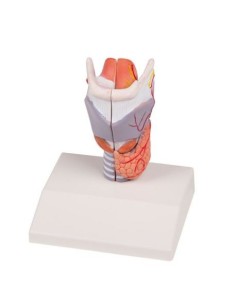

3B Scientifique, modèle anatomique du larynx, deux fois agrandi, en 7 parties G21

3B Modèle anatomique scientifique et fonctionnel du larynx : W42503